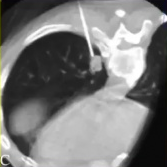

在CBCT成像下的肺病变活检与以前的PET-CT融合

CBCT+PET-CT图像融合引导下活检的操作步骤

3. 基于融合的PET-CBCT数据,计划穿刺针路径指向PET-高代谢的目标

4. 基于这一计划,活检针被定位在实时反馈与目标解剖和配准代谢活动的关系。

5. 使用相同的成像融合方案获得CBCT数据来确认针的定位。

PET-CBCT的融合图像也可以考虑。CBCT可以通过现代血管造影系统获取CT横断面图像。结合专用的软件,使其成功地应用于指导经皮活检。 ![]() 通过工作站把先前患者的PET与CBCT的图像融合进行CBCT引导下的肺活检

通过CBCT经胸经皮肺活检是一种安全且有用的鉴别肺结节的方法。在大多数情况下,在怀疑肺癌的组织学诊断是必要的,以进行靶向治疗和寻找特定的突变。特别是,由融合图像18F-FDG-PET/CBCT提供的解剖和代谢信息提高了组织学诊断的准确性,降低了假阴性的数量和增加获得最终解剖病理诊断的概率。